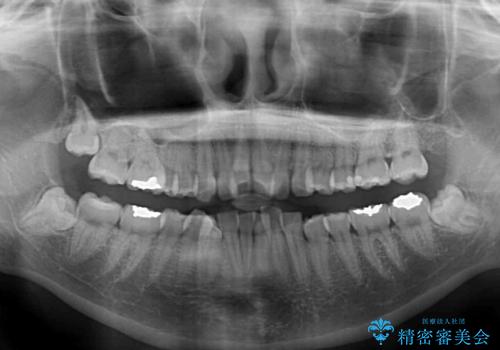

デコボコで飛び出した前歯 ワイヤー装置による抜歯矯正

- 上下前歯のデコボコと、飛び出した前歯を気にして来院された患者様です。

口元を積極的に引っ込めるために、上下左右の小臼歯計4本を抜歯することとしました。

咬み合わせが深く、咬合力強いため、補助装置を使用しながら積極的に口元を下げることとしました。